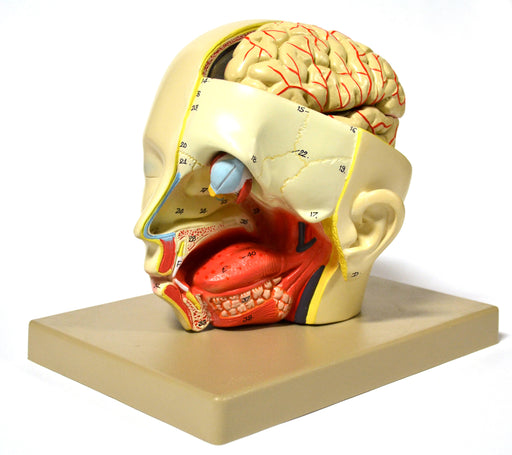

Model, Human, Introductary Head Dissection, removable half brain

Life Size Removable half brain 6 parts Full size model shows major structures of the head. Left side is dissected to show internal structure of ...

View full detailsAM23BAS -